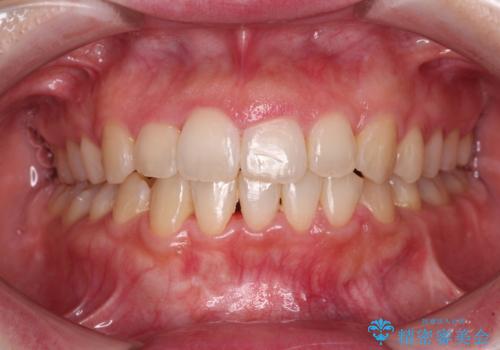

正面や横からの写真ではきれいに治っており、患者様は大変満足のいく仕上がりとなりましたが、深い咬み合わせの改善は不十分で、奥歯の咬み合わせも改善させることができませんでした。

インビザラインは、咬合力の強い方ですと、奥歯が歯肉内にめり込んでしまうため、前歯が強く接触してしまうことがあります。

こちらの方は、奥歯はしっかりと噛んだのですが、歯肉にめり込んでしまったことで、歯肉が腫れやすくなってしまいました。